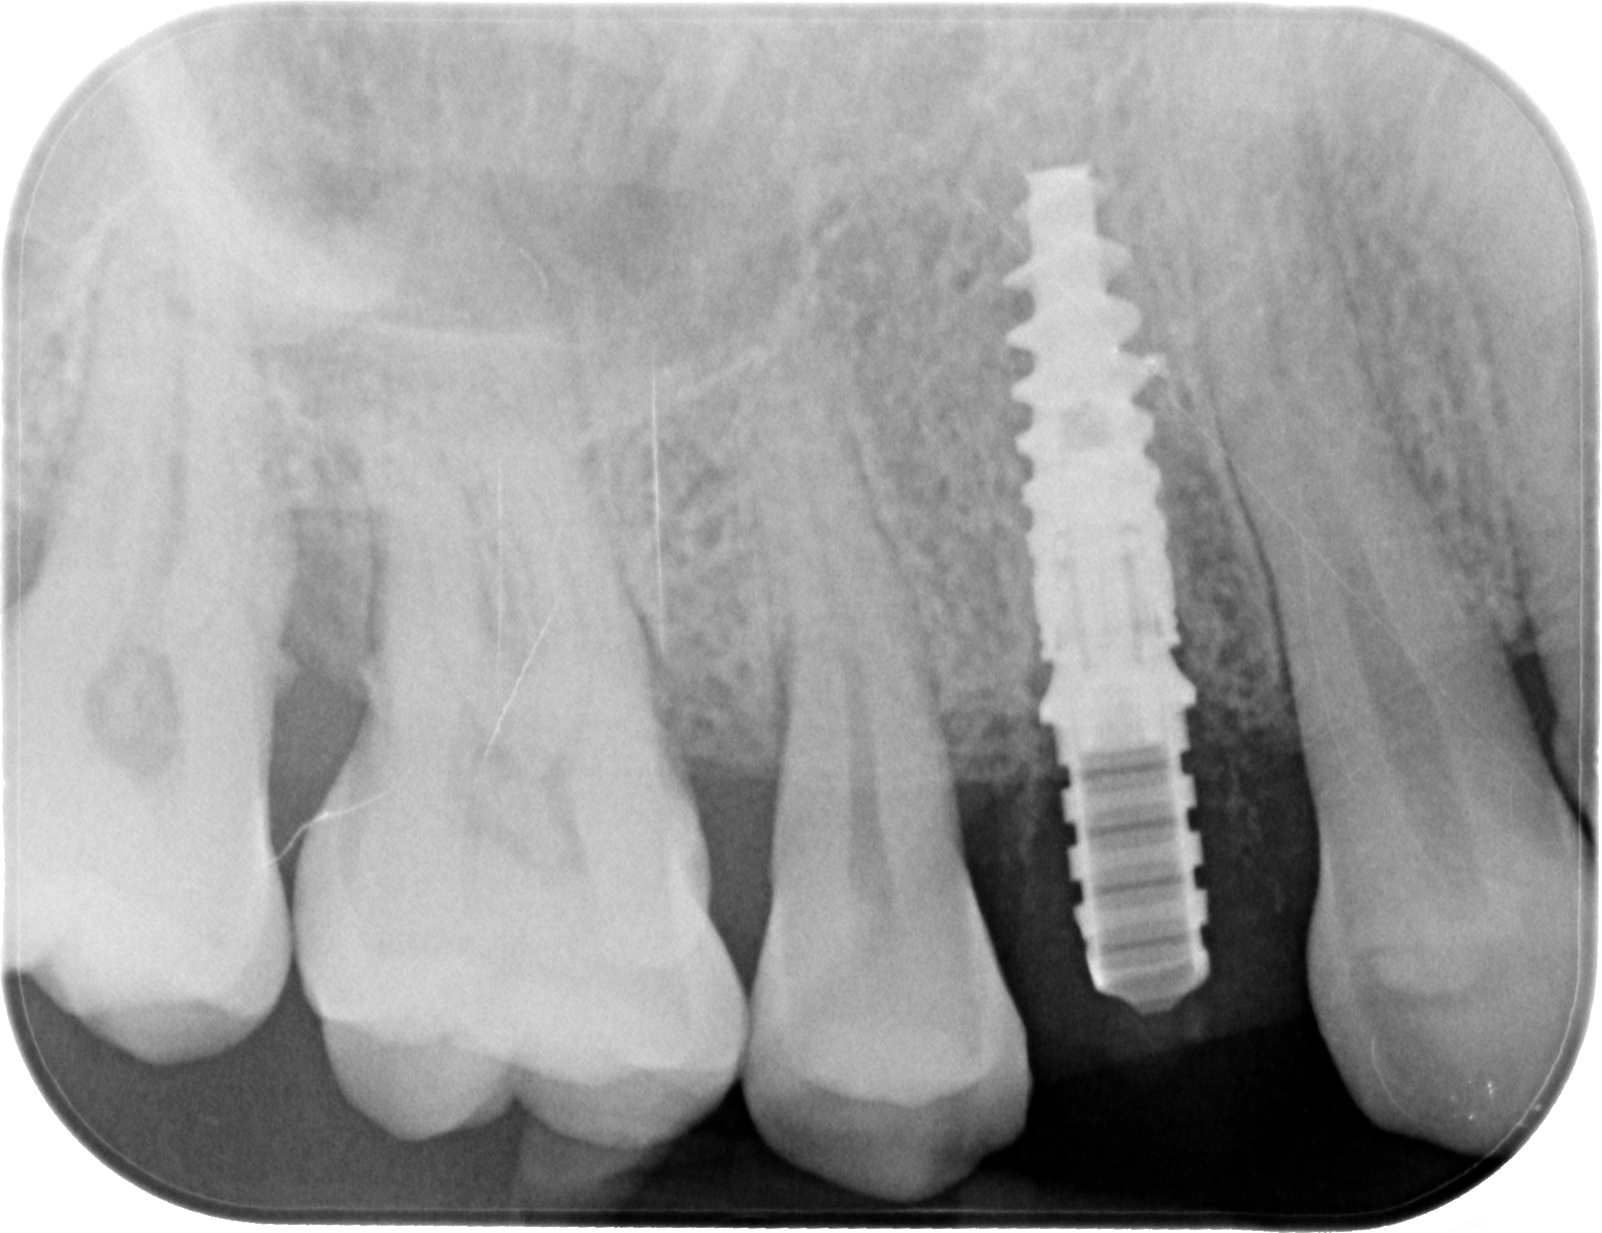

Fig. 02 : radiographie rétro-alvéolaire.

Après l’extraction, la résorption de l’os alvéolaire débute directement influencée par la distance entre la partie externe de la corticale vestibulaire et le col implantaire : plus cette distance est grande, plus le contact os/implant est maintenu coronairement ; plus la corticale est fine et l’implant placé près de celle-ci, plus le risque de déhiscence osseuse et donc de récession gingivale augmente (Araújo et al., 2006)¹. C’est ici que naît la principale critique de l’implantation immédiate : des résultats esthétiques mauvais du fait d’une exposition de l’implant par une résorption de l’os alvéolaire imprévisible. Or, un implant posé dans une alvéole fraîchement déshabitée ne se pose pas comme dans une crête cicatrisée. Pour anticiper la perte tissulaire l’implantation immédiate doit être impérativement associée à un positionnement tridimensionnel idéal de l’implant.